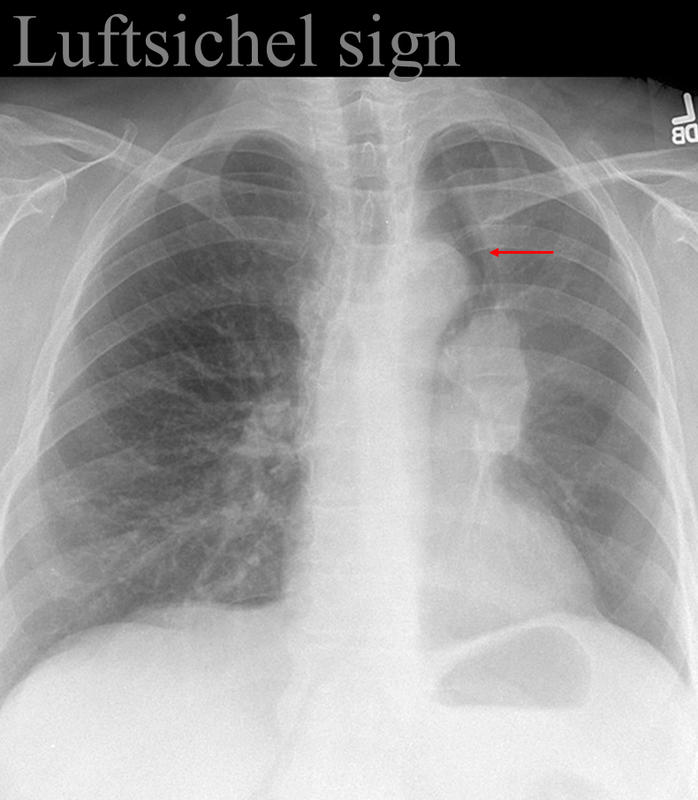

Luftsichel sign

LUL collapse; hyperinflated LLL